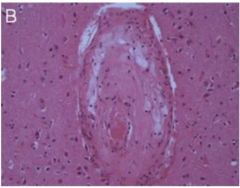

Lipohyalinosis and microatheromas

Front

destructive vessel lesion characterized by loss of nml aterial architecture, mural foam cells; accum of lipid-laden MO w/ in itimal layer of vessel . Assoc with lacunar infarct.

Back